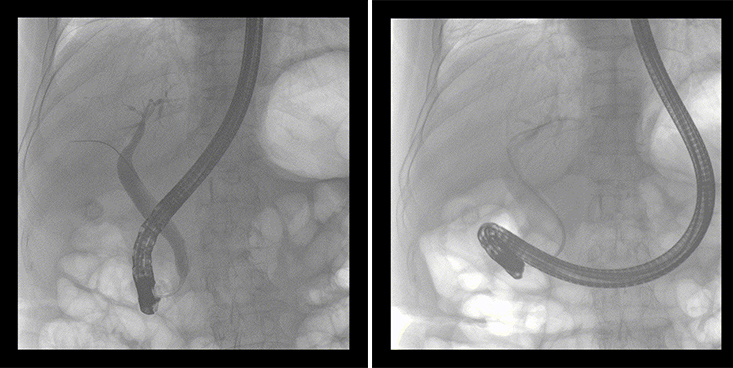

一位86歲的女性患者近來出現(xiàn)腹痛,入院后CT檢查并結(jié)合臨床表現(xiàn)被診斷為急性膽囊炎伴膽囊結(jié)石。經(jīng)專家團(tuán)隊(duì)協(xié)商并與患者家屬溝通,決定對患者實(shí)施經(jīng)內(nèi)窺鏡逆行胰膽管造影(ERCP)。

ERCP(經(jīng)十二指腸鏡下逆行胰膽管造影)現(xiàn)已成為比較成熟的微創(chuàng)介入技術(shù),被廣泛的應(yīng)用于臨床,ERCP也是消化內(nèi)鏡領(lǐng)域難度大、風(fēng)險(xiǎn)大、技術(shù)復(fù)雜的微創(chuàng)手術(shù),其并發(fā)癥多為致命性,ERCP手術(shù)對醫(yī)生的要求很高,因此,ERCP醫(yī)生又被稱為“刀尖上的舞者”。因?yàn)槭中g(shù)難度較大,過程復(fù)雜,需要C形臂精準(zhǔn)的配合,對影像清晰度的要求也非常高。

普愛醫(yī)療移動式平板中C為本次ERCP手術(shù)提供實(shí)時(shí)無損高清影像,幫助醫(yī)生精準(zhǔn)定位?!俺上裥Ч浅0?!完全不輸國際大牌的醫(yī)學(xué)影像設(shè)備……”鼓樓醫(yī)院江北國際醫(yī)院內(nèi)鏡中心手術(shù)團(tuán)隊(duì)對普愛醫(yī)療移動式平板中C的成像效果給與了高度的評價(jià)。

在消化內(nèi)科主任的領(lǐng)導(dǎo)和多科室全力配合下,南京鼓樓醫(yī)院江北國際醫(yī)院成功完成了首例ERCP手術(shù)。